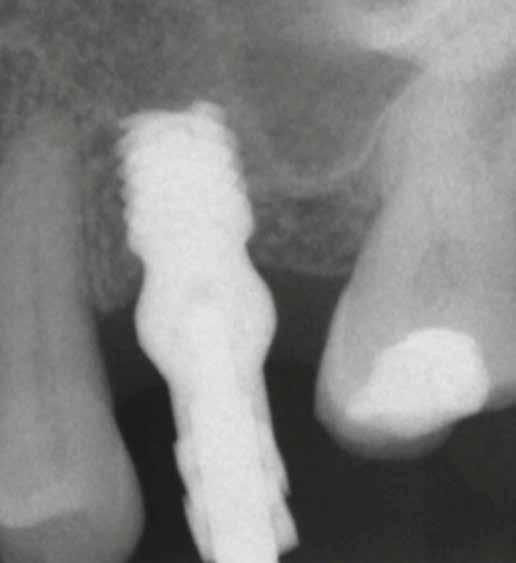

3. a–b ábra: Röntgenfelvételek három hónap után (a) és a gyógyulási csavarok behelyezve (b, 1. eset).

4. a–b ábra: Röntgenfelvételek öt hónappal később (a) és a gyógyulási csavarok behelyezve (b, 2. eset).

5. a–c ábra: Röntgenfelvételek öt hónappal később (a) és a gyógyulási csavarok behelyezve (b és c, 3. eset).

6. a–b ábra: Röntgenfelvételek öt hónappal később (a) és a gyógyulási csavarok behelyezve (b, 4. eset).

8. a–b. ábra: Végső röntgenfelvétel az implantátum helyzetéről (a) és a szájon belüli végső szituáció az 1. esetről (b).

tottuk (az okklúziós koncepciók alapján az implantációs pótlások nem voltak vezető fogak, és csak könnyű érintkezéseket alakítottunk ki, amelyeket artikulációs papírral ellenőriztünk). A páciensek instrukciókat kaptak a megfelelő szájhigiénére vonatkozóan, összpontosítva a fogköz kefékkel történő tisztítására. Végső kontroll röntgenfelvétel készült. A PEEK felépítmény nem radioopák, így az implantátum és a korona közötti távolság könnyen meghatározható a röntgenfelvételen: a felépítmény megfelelően illeszkedik az implantátumban, ha az implantátum válla és a korona alsó széle közötti rés 0,55 mm a röntgenfelvételen (8–11. ábra)